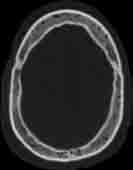

Visible Human male: Sectio transversalis 1037

CT

NMR

Pd T1 T2